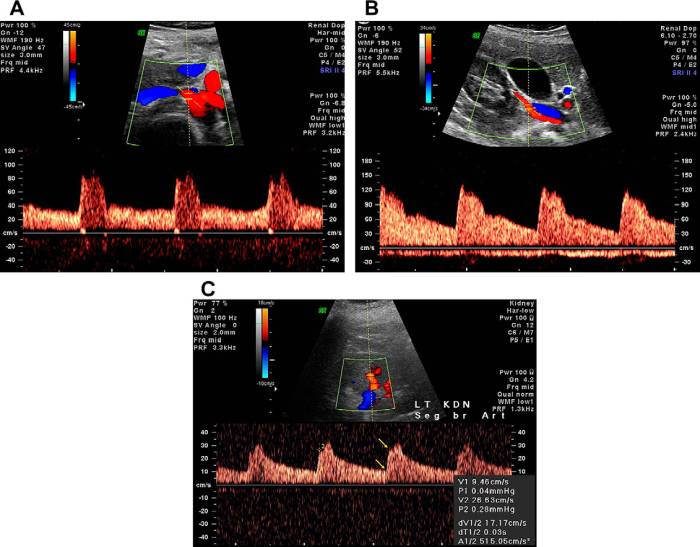

Артерии и вены почек по средствам доплерографии обычно обследуют при:

- Артериальной гипертензии неясного генеза.

- Подозрении на тромбоз этих сосудов.

- Появлении крови в моче.

- Развитии почечной недостаточности.

В ходе доплерографии врач-сонографист обращает внимание на следующие параметры:

- Характер кровотока в исследуемой области (нарушен он или не нарушен).

- Скорость тока крови в периоды сокращения и расслабления сердца (систолы и диастолы соответственно) и соотношение этих скоростей.

- Толщину стенки и диаметр изучаемого сосуда.

- Индекс резистентности и пульсации – это специальные параметры, которые рассчитываются компьютером на основе систолической и диастолической скорости кровотока в сосуде.

- Степень стеноза артерий (на сколько процентов сосуд непроходим).

- Особенности анатомии сосуда (извитость, аневризмы, ветви и т.д.)

Это только общие показатели, по которым оценивается состояние кровотока, УЗИ с доплером того или иного сосуда может иметь свои особенности протокола.